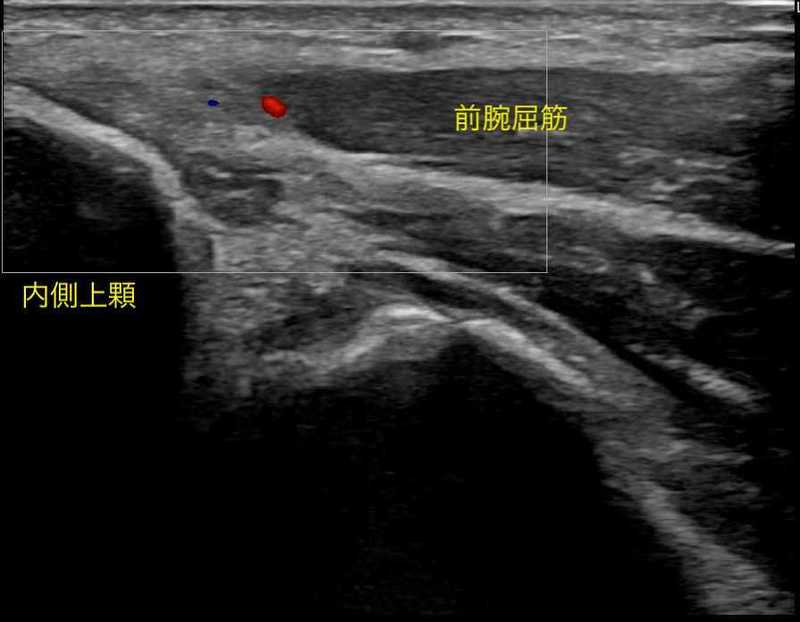

内側上顆炎(別名:ゴルフ肘・テニス肘 内側型)

内側上顆炎は外側上顆炎と同様に肘の内側に付いている筋肉に過剰な負荷がかかり過ぎると腱に痛みが出現します。

日常生活では、手首を手のひらの方向に向けるような動き(掌屈動作)や引っ張るような動きで痛みが出ます。

スポーツ動作では、テニスのフォアハンドで打つときなどで痛みが出現する可能性があります。

この痛みを我慢し続けると、肘の内側いある腱が変性を起こし、痛みが持続してしまいます。

症例提示

【年齢】50歳 【性別】男性

2021年6月ごろ テニス時に肘関節内側部に疼痛出現。

特にテニスの練習(フォアハンド・サーブ)中〜練習後に疼痛を認めた。

以前から手関節、肘関節、肩関節に疼痛を認めることはあったが

今回疼痛が強いため2021年12月受診。リハビリと併用して拡散型衝撃波を実施。

下に治療中の疼痛推移を示します。

体外衝撃波は2回施行し、漸減的に疼痛が軽減していきました。

テニスにも復帰でき、通院終了となりました。

縦軸:痛みの強さ 最も痛い→10 痛くない→0

横軸:時間軸